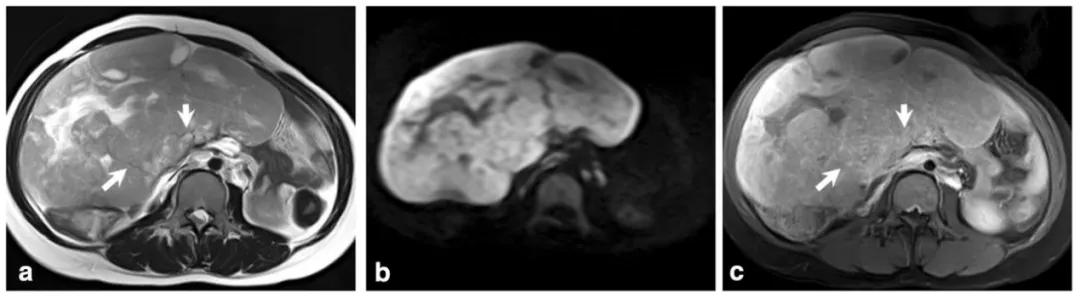

女,75 岁,浆液性癌。CA-125 升高。双侧卵巢不规则肿物,与腹膜结节分界不清,T2WI 呈不均匀稍高信号(图 a),DWI 呈不均匀高信号(图 b),CT 显示肿物内钙化(图 c)。箭头显示左侧髂血管旁转移淋巴结。

女,22 岁,无性细胞瘤。乳酸脱氢酶及碱性磷酸酶升高。T2WI 示右侧卵巢分叶状肿物(图 a),DWI 呈高信号(图 b),增强扫描明显强化(图 c)。箭头显示肿物内可见纤维血管分隔。

女,18 岁,卵黄囊瘤(右侧),AFP 升高。T2WI 示卵巢实性为主肿物(图 a),内见低信号纤维血管分隔(白箭),实性成分 DWI 呈高信号(图 b),增强扫描明显强化(图 c),内见无强化坏死区(箭头)。